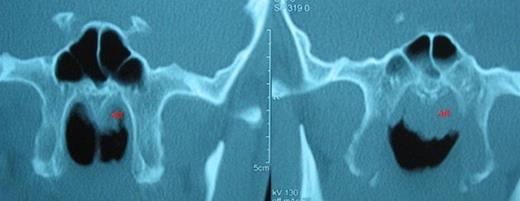

The patient underwent endonasal endoscopic surgery with the diagnosis of rhinolithiasis. The rhinolith was successfully removed with minimal possible injury to surrounding nasal mucosa. The nasal cavity was irrigated with saline. After removal of the rhinolith, adenoid hypertrophy was prominent on the left side (Figure 3). Adenoidectomy was subsequently performed and postoperative histopathologic examination revealed lymphoid hyperplasia and chronic inflammatory cell infiltration without any malignant transformation.

a) Right nasal cavity; clinically insignificant lymphoid hyperplasia on the nasopharynx. b) Left nasal cavity; clinically significant adenoid hypertrophy. it: inferior turbinate, ad: adenoid hypertrophy, Nx: Nasopharynx.